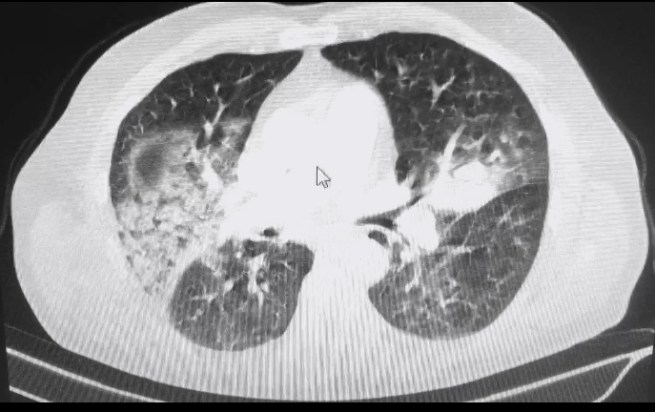

Imagem: Síndrome Respiratória Aguda Grave pelo vírus influenza H3N2